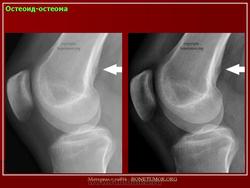

Рентгенологическая картина остеоид-остеомы весьма характерна. Рентгенологические симптомы возникают значительно позже клинических проявлений опухоли, и первым на рентгенограмме обнаруживают склероз кости. На участке поражения формируется одностороннее или муфтообразное утолщение кости в виде гиперостоза. Позднее в толще гиперостоза формируется основной отличительный признак остеоид-остеомы - ее «гнездо» в виде очага разрежения диаметром до 1 см, внутри которого могут отмечаться мелкие костные включения. Сквозь слой склерозированной ткани «гнездо» опухоли на обычных рентгенограммах не всегда дифференцируется и для ее выявления применяют лучи повышенной жесткости и томографию. Обнаружение «гнезда» необходимо для подтверждения диагноза и проведения направленного оперативного вмешательства.